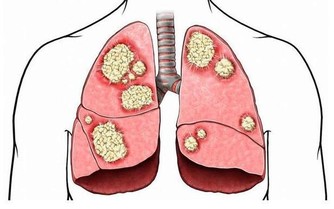

5. 你罹患某些癌症的風險更高

你可能正在想盡一切辦法預防癌症,那麼,讓硒保持最佳水平吧。

因為,它可以讓胃癌、膀胱癌和前列腺癌的風險降低31%,反之則會增加其風險。